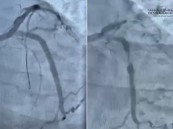

مستشفى الحبيب بالخبر ينقذ حياة مراجع توقف قلبه بسبب انسداد كلي للشريان النازل

بفضل من الله- نجح مستشفى الدكتور سليمان الحبيب بالخبر، في إنقاذ حياة مريض خمسيني توقف قلبه، إثر إصابته باحتشاء في عضلة القلب، وتمكن فريق طبي قاده د. عبدالله الشهري استشاري القلب والقسطرة التداخلية، من إنعاشه واستعادة حركة الدم الطبيعية في ...